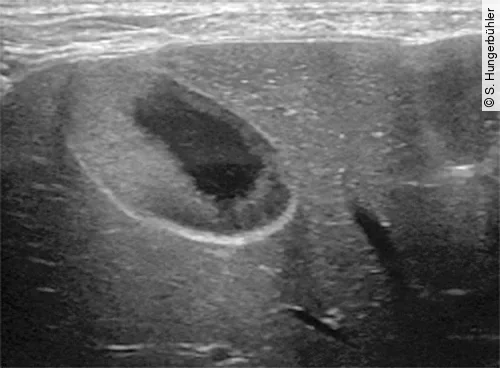

In der Literatur werden verschiedene Stadien der MZ beschrieben. Zu Beginn liegt sonografisch eine verdickte Mukosa entsprechend der pathohistologisch beschriebenen Hypertrophie vor. Die ansonsten dünne hyperechogene Linie der GB-Wand zeigt bei diesen Patienten eine raue, echoarme lumenwärts gelegene Schicht. Bei guter Bildauflösung können in der verdickten Mukosa feine echogene Lamellen erkannt werden (Abb. 2).

Im Lumen befindet sich häufig echogener Sludge, der wenig oder nicht mobil ist und der verdickten, echoarmen Mukosa aufliegt. Die GB ist im Frühstadium einer Mukozelenbildung unterschiedlich stark gefüllt. Im Verlauf nimmt die Füllung aufgrund der verminderten Motilität progressiv zu. So zeigten Hunde mit MZ 60 und 120 min nach Fütterung eine im Vergleich zu gesunden Hunden signifikant verminderte Ejektionsfraktion [13].